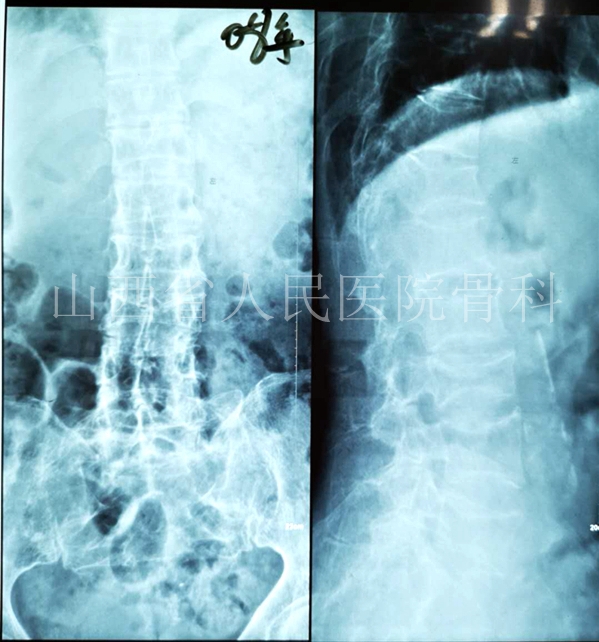

2008年5月因腰背疼痛检查发现T12、L3压缩骨折

患者选择保守治疗及抗骨质疏松治疗。但是在2012年再次发生腰背疼痛,此时的患者依旧选择保守治疗。

2012年3月腰背疼痛加剧检查发现T12、L3压缩骨折+L2、L5新发压缩骨折